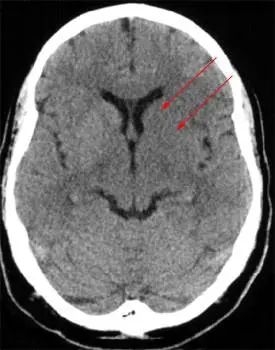

李先生的影像学报告结果显示:左侧豆状核模糊。这是最早及最常见的脑血管堵塞征象之一,见于大脑中动脉梗塞。

对此,脑科专家指出:高血脂在前期通常不会造成明显不适,但会在不知不觉中损害血管健康。李先生的这些症状都是早期脑部血管堵塞的症状,一定要引起重视。